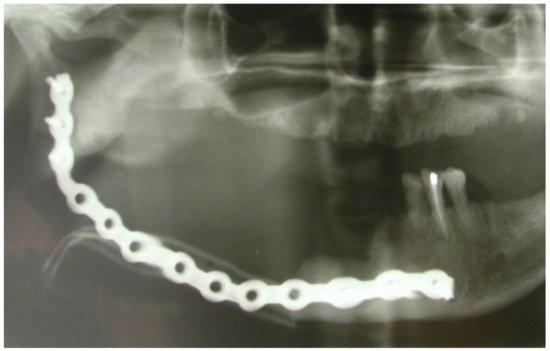

3.1. Clinical Case 1